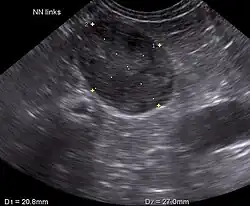

Sonographic image of the left adrenal gland in a dog with adrenal hyperadrenocorticism

Ultrasonography, CT scans, and MRI are used to identify any abnormality in the pituitary or adrenal gland. This helps diagnose if the patient has pituitary-dependent Cushing's or adrenal-dependent Cushing's.[2]